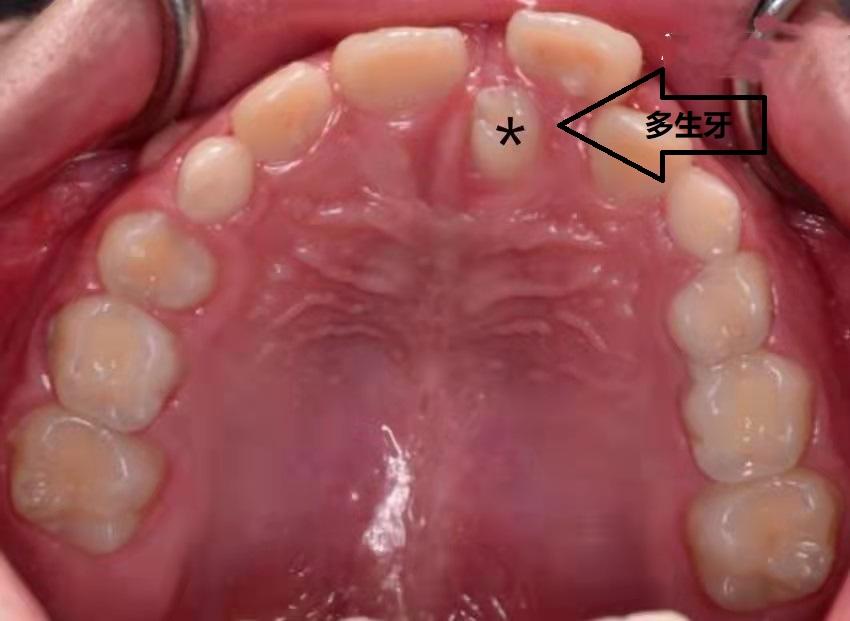

原因三:多生牙

上前牙区是多生牙发生的常见部位,如果多生牙恰好长在了中切牙之间,就会造成中切牙之间的缝隙。部分多生牙生长方向与正常牙齿相同,可以自行萌出;但是大多数多生牙的方向并不与正常牙齿一致,不能自行萌出,只能通过口腔检查拍X光片时发现。如果有多生牙存在,影响了正常牙齿的生长,就需要及时就诊拔除。